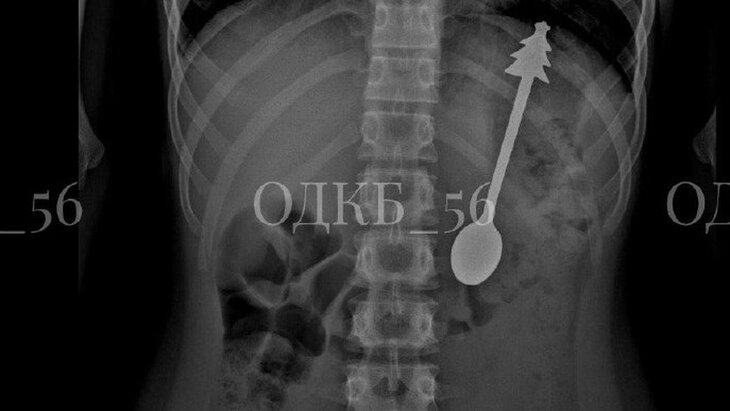

Фото: Оренбургская областная детская клиническая больница

Врачи выяснили, что ребенок случайно проглотил ложку. По итогам рентгенографии они подтвердили наличие металлического предмета в области желудка. Пациент был направлен на экстренную операцию.

В ходе вмешательства, проходившего в условиях общего обезболивания, медики успешно извлекли ложку при помощи эндоскопа. Длина столового прибора составила 14 сантиметров.